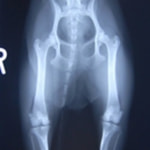

■ 症例22 ポメラニアン 1歳5か月 去勢雄

左後肢の挙上を主訴に来院した。整形学的検査、レントゲン検査より左右の膝蓋骨脱臼(左GradeⅡ〜Ⅲ、右Grade Ⅱ)を認めた。また、脛骨の前方引き出し試験の際に、引き出し兆候は認められないものの、疼痛が認められたため、前十字靭帯の損傷が疑われた。術中における、目視および関節内の操作によって、前十字靭帯の損傷や過伸展といった異常が認められなかったため、膝蓋骨脱臼の整復のみ実施した。手術手技は縫工筋及び内側広筋の解放、脛骨粗面の外側転位、滑車ブロック形造溝術、内外側関節包の縫縮を実施した。本症例は跛行もなく経過良好である。しかし、頸骨高平部の角度(TPA)が 右26.2°、左24.9°であり、解剖学的に前十字靭帯損傷のリスクが高いことから今後の経過に注意が必要である。